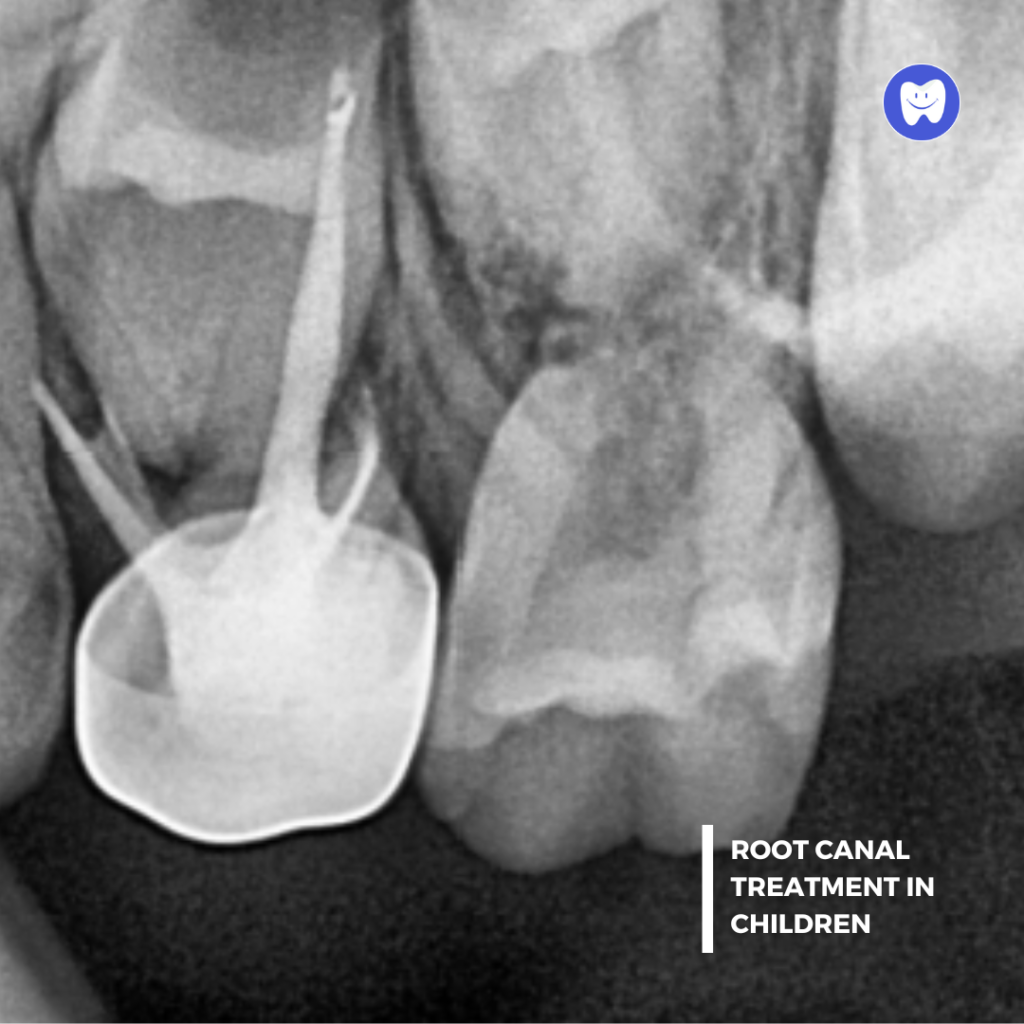

Periapical X-Rays

Focuses on the details of one or two teeth, including the roots.